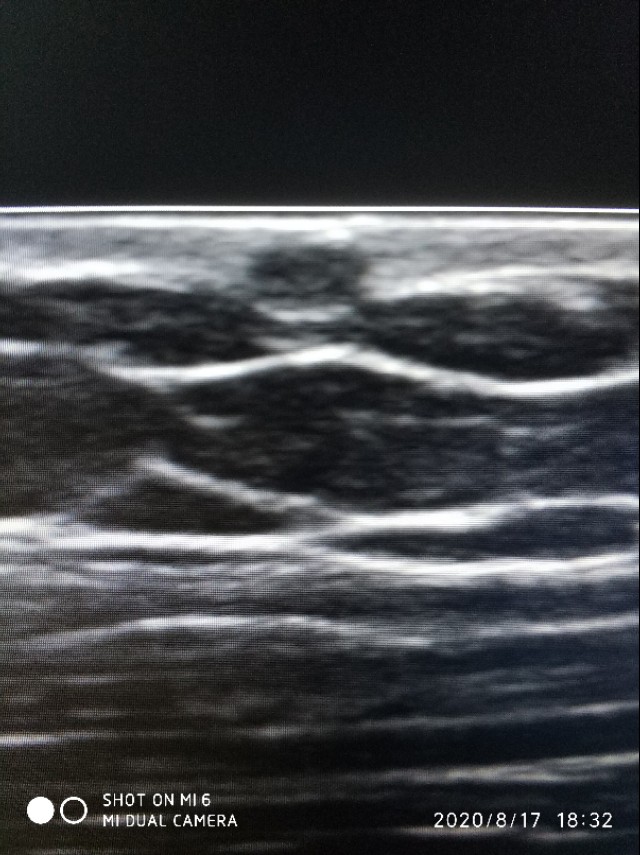

上面是我大腿上的皮脂囊肿,奉献给大家啦。在皮肤上有个小黑点,以前我总是手贱,喜欢抠它挤它,有豆腐渣样的东西出来,至于是什么味道,大家自行脑补。因为害怕有癌变的可能,我现在碰都不碰它了。有些皮脂囊肿增大感染的,其实我也没怎么碰到过,可能没来做超声直接被医生挖掉了。

上图表皮层忽略不计,真皮层为回声增强的一层,再下方是黑白相间的脂肪层,再往下是肌肉层了。